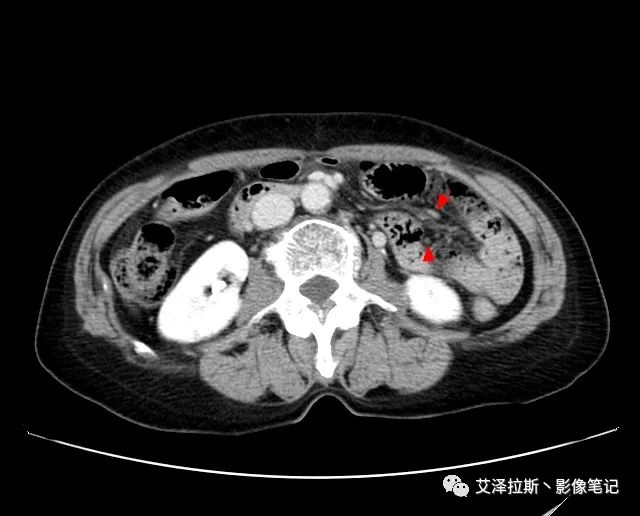

【影像所見】 胃竇部狹窄,胃壁環形增厚,小彎側見一巨大潰瘍,周圍伴“環堤征”,漿膜面不完整,胃周脂肪見網格狀條索影,病灶與肝臟左葉、胰腺鉤突脂肪間隙消失,增強掃描病灶明顯強化。引流區內約15個區域淋巴結受累。

【診斷意見】 胃竇部胃癌(T4N3期) 該病例腫塊突破漿膜層,與肝臟左葉、胰腺鉤突分界不清,脂肪界面消失,定為T4期; 受累及的淋巴結為15個區域,定為N3; 有無遠處轉移尚不明確,所以M期暫時無法確定。